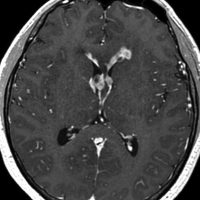

ガドリニウム増強では,前頭葉腫瘍というより,側脳室壁にベトベトくっついているような腫瘍です。germinoma特有のsubependymal infiltration像を示します。

左はICE化学療法 (IFO/CDDP/VP-16)前,右は1コース終了後です。腫瘍は顕著に縮小してgerminomaとして普通の化学療法反応性を示します。また,松果体と下垂体には腫瘍はありません。